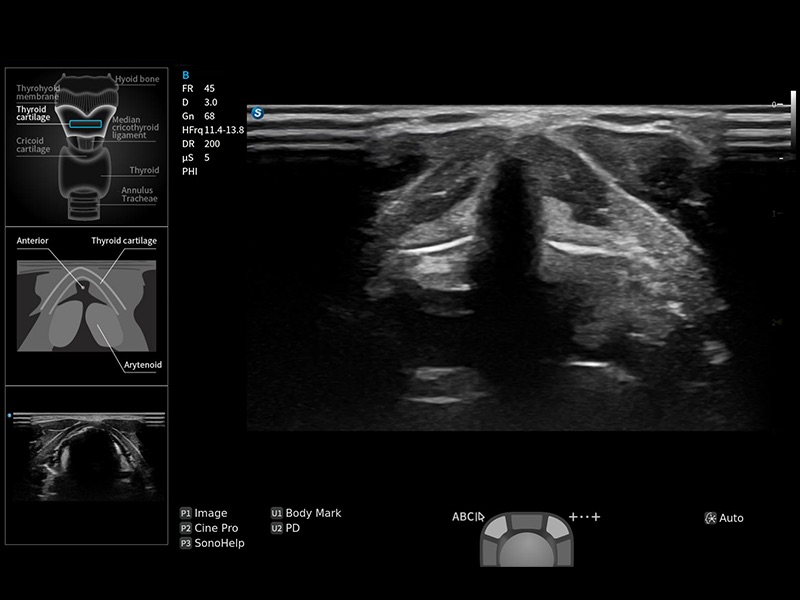

指导操作者进行标准切面的正确扫查,涵盖丰富应用场景,为新晋医生提供实用的参考指导。